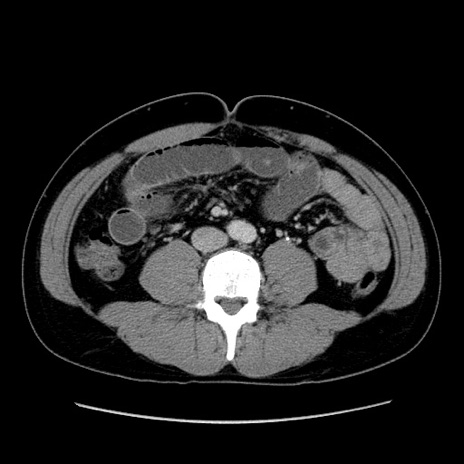

症例4(横断像)

【症例】30歳代男性

【主訴】腹痛、嘔吐

【現病歴】昨晩から突然の腹痛あり、その後嘔吐、軟便も出現。腹痛が改善しないため救急搬送となる。2日前にしめ鯖の食事歴あり。

【身体所見】意識清明、苦悶様、BP 135/90mmHg、BT 35.7℃、腹部:平坦、やや硬、心窩部〜臍部に自発痛、圧痛あり、筋性防御+、反跳痛-

【データ】WBC 8100、CRP 0.57